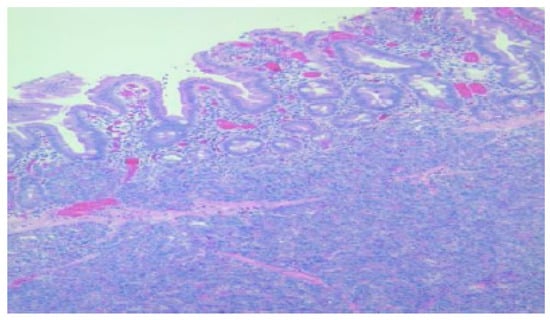

According to the Heinrich classification, modified by Gaspar-Fuentes et al., there are four histological types of EPT: type I—presenting acini, ducts, and islets (complete heterotopia), type II—presenting only ducts (canalicular heterotopia), type III—presenting only acini (exocrine heterotopia), and type IV—presenting only islets (endocrine heterotopia) [19]. 5 out of the 6 cases evaluated belonged to type I and 1 case belonged to type III (Figure 1, Figure 2, Figure 3 and Figure 4).

Figure 1. Detail with exocrine serous acini in the ectopic pancreatic tissue, HE, 200×.